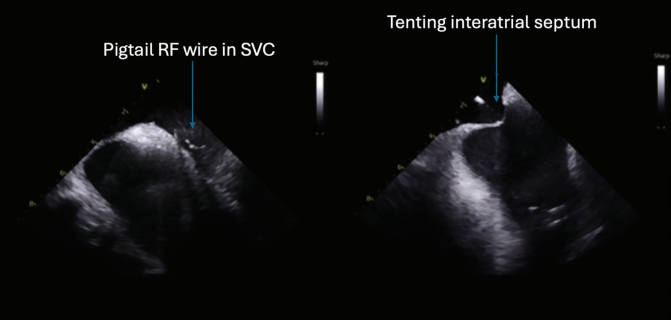

diagnosed 1.5 years prior. He was previously cardioverted and maintained on dronedarone with recurrence of symptomatic persistent AF, prompting referral for catheter ablation. He subsequently underwent AF ablation utilizing a pentaspline catheter. Ultrasound guidance was utilized to obtain 3 points of vascular access in the right femoral vein (Figure 1). ICE guidance was utilized for transseptal access and to guide catheter manipulation while ensuring optimal contact with ablation (Figures 2 and 3). Meticulous sheath management was employed, ensuring performance of all sheath exchanges while aspirating to reduce likelihood of air bubble introduction. A baseline electroanatomic voltage map was obtained for a substrate-based approach, which showed a predominantly healthy left atrium despite persistent AF though notably early in its course (Figure 4). There was spontaneous induction of AFL with a cycle length of ~280 ms and response to entrainment and activation mapping most consistent with typical AFL. The decision was made to proceed with PV isolation with confirmation of antral level isolation without significant encroachment on the posterior wall on a post-ablation voltage map (Figure 5). The cavotricuspid isthmus line was outlined on the EAM system with ICE while ensuring the intended ablation path was not in direct proximity to the right coronary artery. Ablation was then performed utilizing the pentaspline catheter in flower configuration after pre-administration of nitroglycerin and phenylephrine with termination of AFL and demonstration of bidirectional block post ablation. Total fluoroscopy time was ~4 minutes, the majority of which was utilized for the typical flutter ablation. The patient tolerated the procedure well and was discharged home 6 hours later. He continues to do well in outpatient follow-up.

Highlighted in this case are key tenets in our procedural approach to PFA. First, similar to other ablation technologies, the majority of complications are usually vascular in origin. These complications are largely mitigated with appropriate ultrasound guidance technique to vascular access, as was demonstrated in the MANIFEST-17k registry.16 The need for meticulous sheath management to reduce air bubble introduction cannot be overstated given the large sheath profiles utilized, to reduce the risk of stroke and coronary air embolism. We maintain that ICE guidance and EAM play a pivotal role in guiding ablation. This is important to ensure adequate contact for optimal energy delivery as there is increasing data highlighting its importance for durability.17

Additionally, the ease of ablation with these large footprint PFA catheters also raises concern of collateral damage to neighboring healthy myocardium such as the posterior wall when perhaps only PVI is the intent. This effect in some instances can be proarrhythmic. The ability provided by these tools comes with significant responsibility to be judicious with ablation lesions which can certainly be better optimized with EAM and ICE guidance. The clinical impact of this will likely be better delineated as we have large-scale, long-term follow-up data. Additionally, ICE and EAM guidance also facilitate a low or no fluoroscopy workflow as there is more data being published on the feasibility of this approach.18 This builds upon the significant trend towards zero-fluoroscopy procedures with thermal ablation platforms, which impact both the patients and EP team.